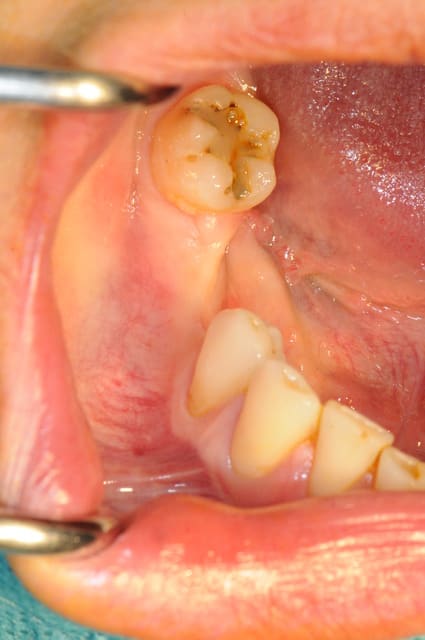

CAS 1

demande de restauration avec implant, mais, ne veut pas entendre parler de greffes et greffons.

la ROG lui semble plus "naturel".

photos

1-2-3 situation de départ

4 après ouverture